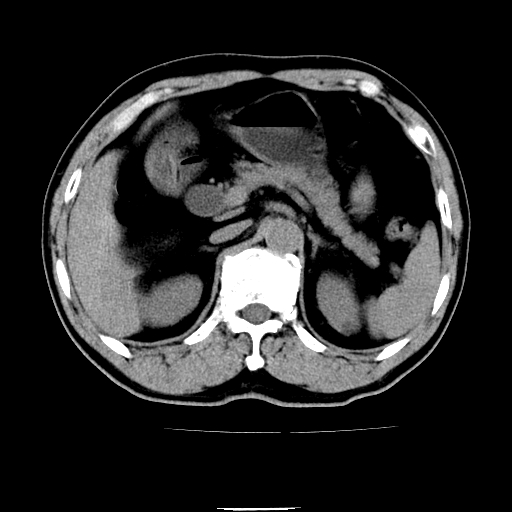

以下是引用chenqiong在2010-3-25 20:56:00的发言:[br]1、胆囊炎,胆囊息肉[br]2、肝内胆管及胆总管扩张,胆总管下端结石[br]3、十二指肠乳头旁憩室

以下是引用zxl51642在2010-3-26 10:47:00的发言:[br]胆囊炎,胆囊息肉,胆总管扩张,但未看到明显肿块,肝内胆管扩张不像恶性,炎性狭窄或阴性结石可能吧,建议mrcp,右肾小囊肿